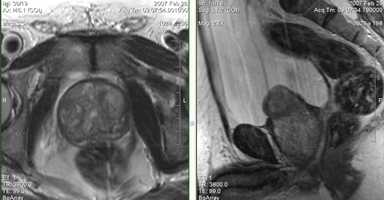

а) Т2-tra б) Т2-sag

Хорошо визуализируется зональная анатомия простаты, выраженная гиперплазия переходной зоны неоднородной структуры, компрессия периферической зоны на этом фоне. Переходная зона вдается в просвет мочевого пузыря (б).